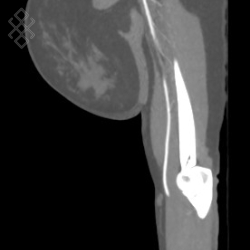

Angioscanner des Membres supérieurs